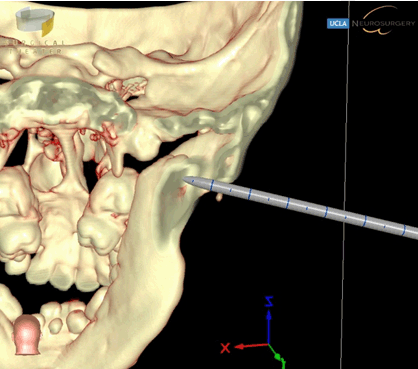

Prior to her last surgery, the patient had reankylosis of her bilateral TMJ resulting in severe limited jaw opening that required repeat mandibular osteotomies (Figure 1). For the previous mandibular osteotomy, Brainlab intraoperative CT-guided navigation system was used to aid in the preoperative planning of localizing and assessing the extent of the TMJ fusion. The surgery was completed in nine hours with no complications. For most recent mandibular osteotomy, SuRgical PlannerTM was used in conjunction with Brainlab intraoperative CT-guided navigation system (Figure 2). This additional surgical guidance tool allowed us to rehearse the operation for TMJ resection and also assess the extent of our dissection, thereby accelerating operative efficiency (Figure 3). Additionally, based on principle of CT scanning Hounsfield unit, the SRP simulator can display or hide slices of tissue in real time, thereby allowing us to visualize surrounding skull base, vessel, and soft tissue anatomy as well as the location of our surgical probe to minimize skull base complications [12]. Overall, the operative time was four hours, a notable decrease from nine hours previously. There were similar scars noted from prior surgeries and no complications. The exact same sequence of surgery and placement of Matthews device was performed for these two operations to justify the comparison.

Figure 3: Coronal view of 3D precision VR showing extent of temporamandibular joint ankylosis surgical entry in relation to position of instrument probe. This allowed surgeon to manipulate the model to exact slice and orientation, allowing quick and accurate spatial location of extent of surgical dissection, speed and accuracy compared to navigating off of three 2D slices.